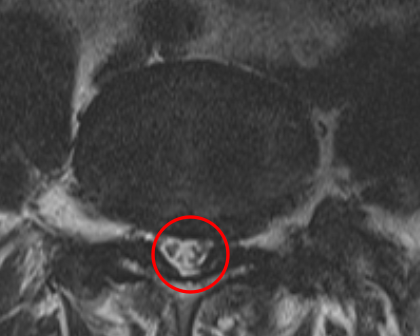

腰痛の原因を調べるため腰椎MRI画像を確認したところ、赤い枠内(L4/5)に椎間板ヘルニアが見つかりました。これが椎間板を圧迫して、腰痛が出てしまっていると考えられます。